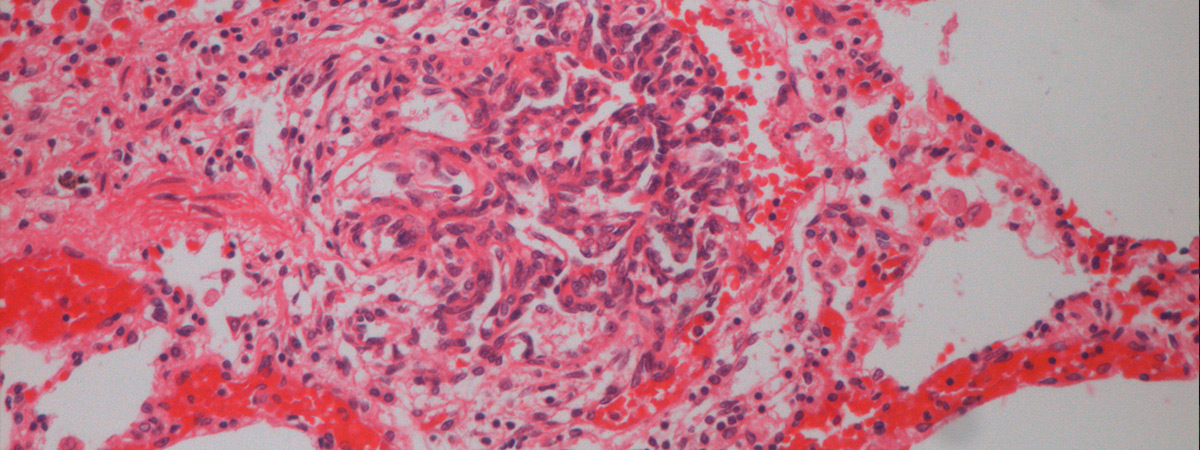

Idiopathic and heritable forms of pulmonary arterial hypertension (PAH) are devastating conditions associated with high morbidity and mortality. The disease is usually diagnosed late by finding a markedly increased pulmonary arterial pressure (increased blood pressure in the arteries of the lungs), the result of progressive narrowing and obliteration of the pulmonary vasculature, which often results in failure of the right ventricle. This disease tends to present in the middle decades of life, with a female predominance.

A major breakthrough in our understanding of the molecular basis of hypertension PAH was the identification of heterozygous germline mutations in the bone morphogenetic protein type II receptor (BMPR-II) in the majority (>70%) of familial cases of the disease and a significant proportion (15-26%) of sporadic cases. Although the presence of mutations in BMPR-II is the greatest risk factor for the development of PAH, it is estimated that only 20% of carriers develop the disease. Additional factors are required for disease manifestation. These may be genetic and/or environmental, though the identity of these factors remains unknown.